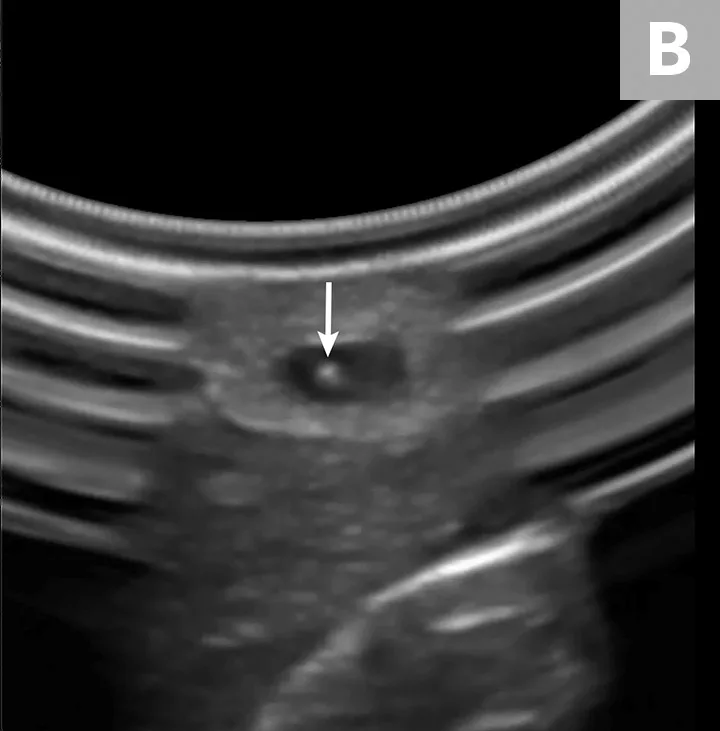

Place the probe on the skin at a 90-degree angle to the vessel (A). Use probe manipulations (eg, sweeping, sliding, rocking, fanning) to identify and situate the vessel (B, arrow) in the horizontal center of the ultrasound display.

Gloved hands holding ultrasound probe over limb of pet and ultrasound image with arrow pointing to blood vessel.

Insert the catheter needle and stylet into the skin at a 30- to 45-degree angle, just distal to the probe (A). Identify the needle tip as a white dot (B, arrow) on the display between the skin and the vessel, and stop advancing.

Ultrasound probe held over limb of pet and ultrasound image with arrow pointing to needle seen within blood vessel.